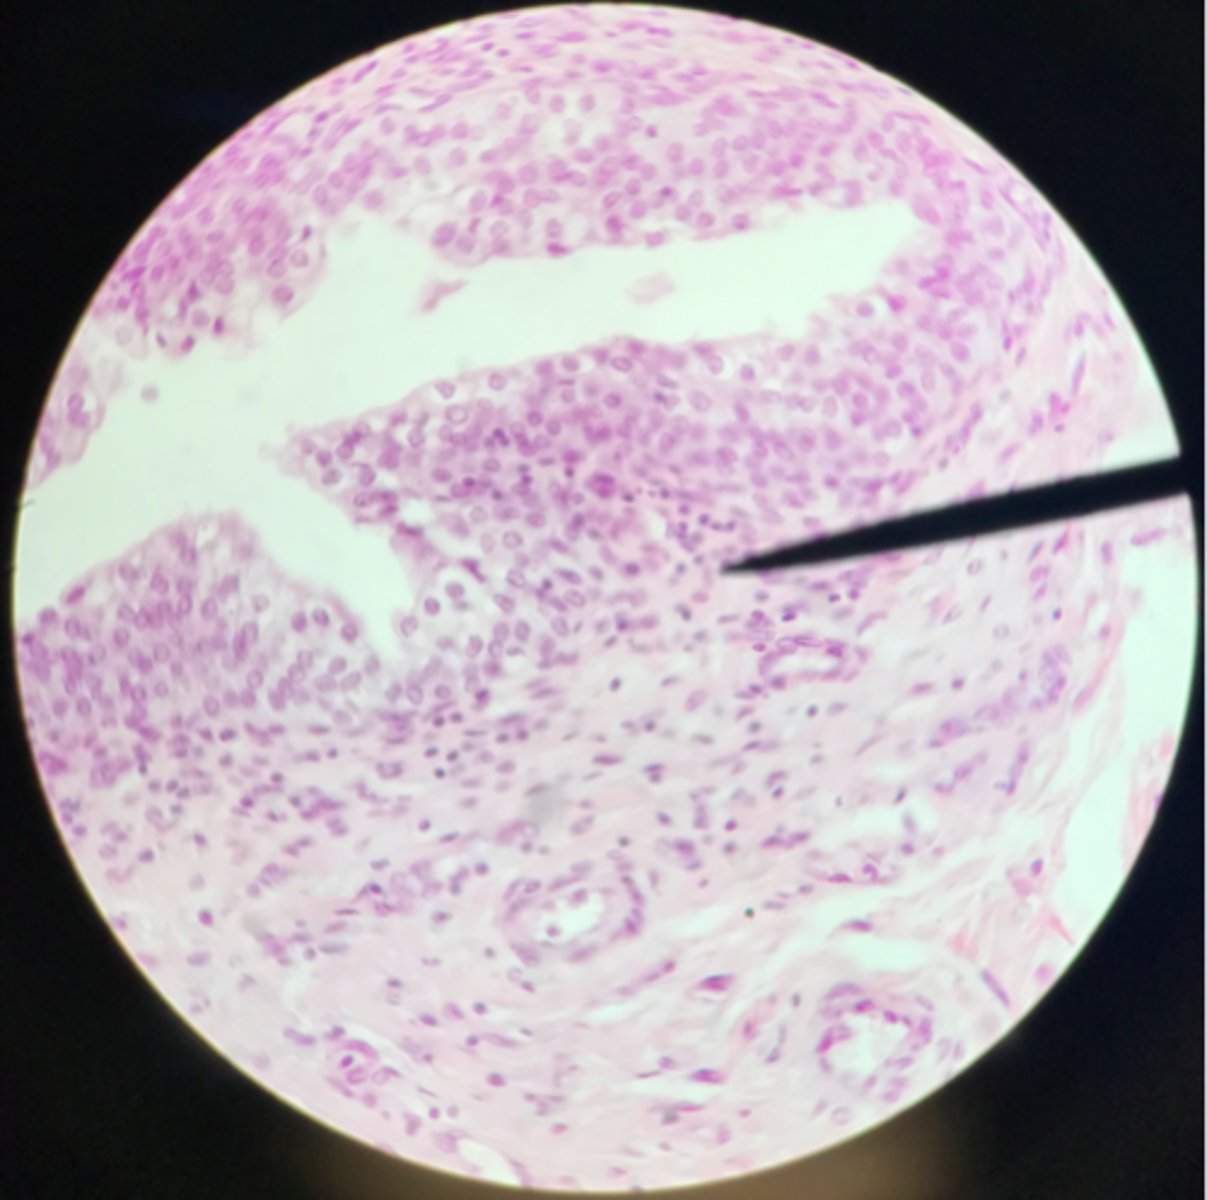

Transitional epithelium of the bladder

What tissue is depicted on the slide above the pointer?

Basement membrane

What cells of transitional epithelium are located where the pointer is at?

Ureter

Transitional epithelium

What structure/organ is depicted on this microscope slide?

What tissue makes up a majority of it?

Transitional epithelium

What type of tissue makes up the inner lining of the ureter?

Urinary bladder

Transitional epithelium

What organ is depicted on the slide? What type of tissue is the main component?

Ureter

Note the smooth muscle layer surrounding the transitional epithelium

What organ is depicted on this slide?